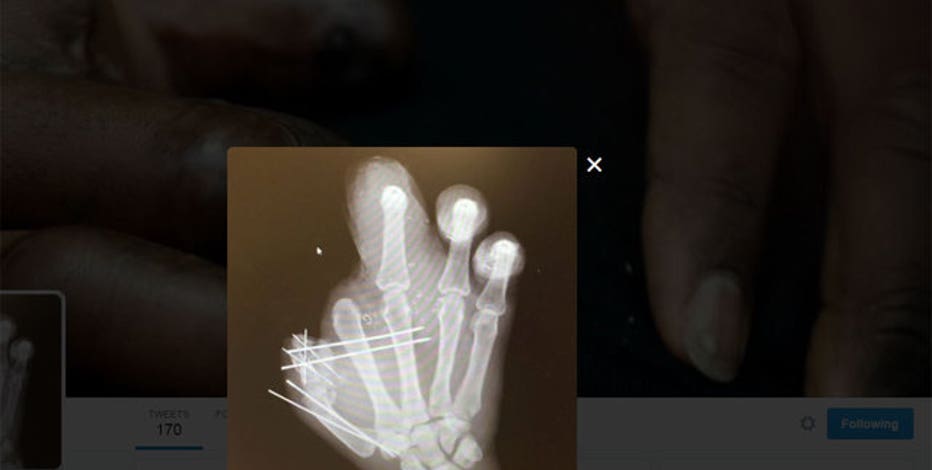

According to Pierre-Paul's lawyers, Mitchell Schuster and Kevin Fritz, Schefter "improperly obtained" the defensive end's medical chart, which showed he had his right index finger amputated at Jackson Memorial Hospital in Miami.

Schefter posted a photo of Pierre-Paul's chart on July 8 on Twitter, where he currently has more than 4.5 million followers.